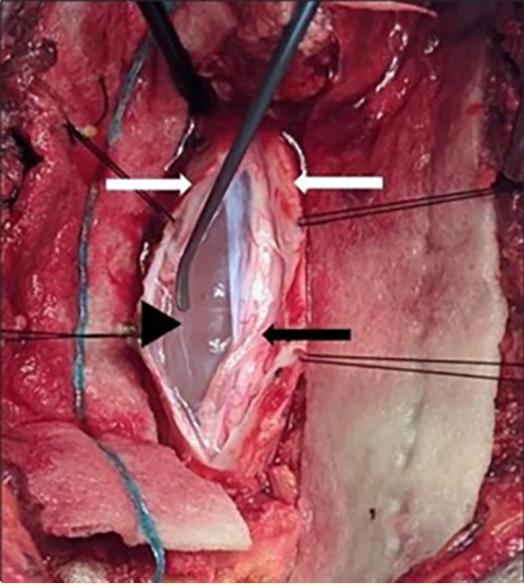

在荧光镜定位的帮助下,进行了T5-T6和T6-T7椎板切除术,并在术中超声检查的帮助下确认了囊肿的头尾部范围(图2)。分离第五和第六左侧肋间神经,以便于硬脑膜的活动,沿着硬脑膜袖的线打开硬脑膜。硬膜内髓外蛛网膜囊肿被确认并使用显微外科技术切除(图3)。减压后,脊髓在术中再次扩张。

图3、术中观察(通过椎板切除术)胸椎硬膜内髓外蛛网膜囊肿。白色箭头表示切开硬脑膜的回缩边缘,黑色箭头表示蛛网膜囊肿,黑色箭头表示脊髓受压